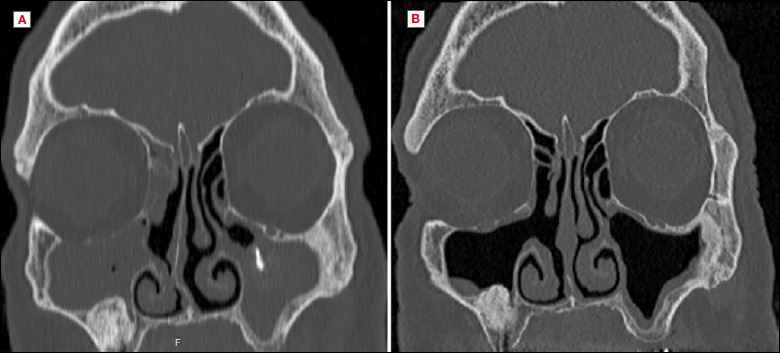

Materials and methods: Medical records of patients who underwent SIMA for maxillary sinus pathologies were retrospectively reviewed. Data collected included age, gender, presenting symptoms, preoperative and postoperative endoscopic and computed tomography findings, early follow-up duration, and complications.

Results: Twenty-two operated maxillary sinuses, in 20 patients, were included. Pathologies included displaced dental implant (n = 4), odontogenic sinusitis (n = 6), retention cyst (n = 5), antrochoanal polyp (n = 5) and fungus ball (n = 2). SIMA provided excellent access and view, and the OMC and the inferior meatus mucosa remained intact. Nineteen patients were completely cured following a rapid recovery and needed no further intervention. No intra-operative or postoperative complications occurred, and recirculation was not observed. One case failed due to a persistent odontogenic infection.